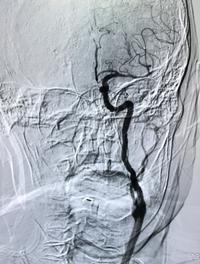

La thrombectomie mécanique endovasculaire a transformé le pronostic fonctionnel des accidents vasculaires cérébraux (AVC) ischémiques [...]